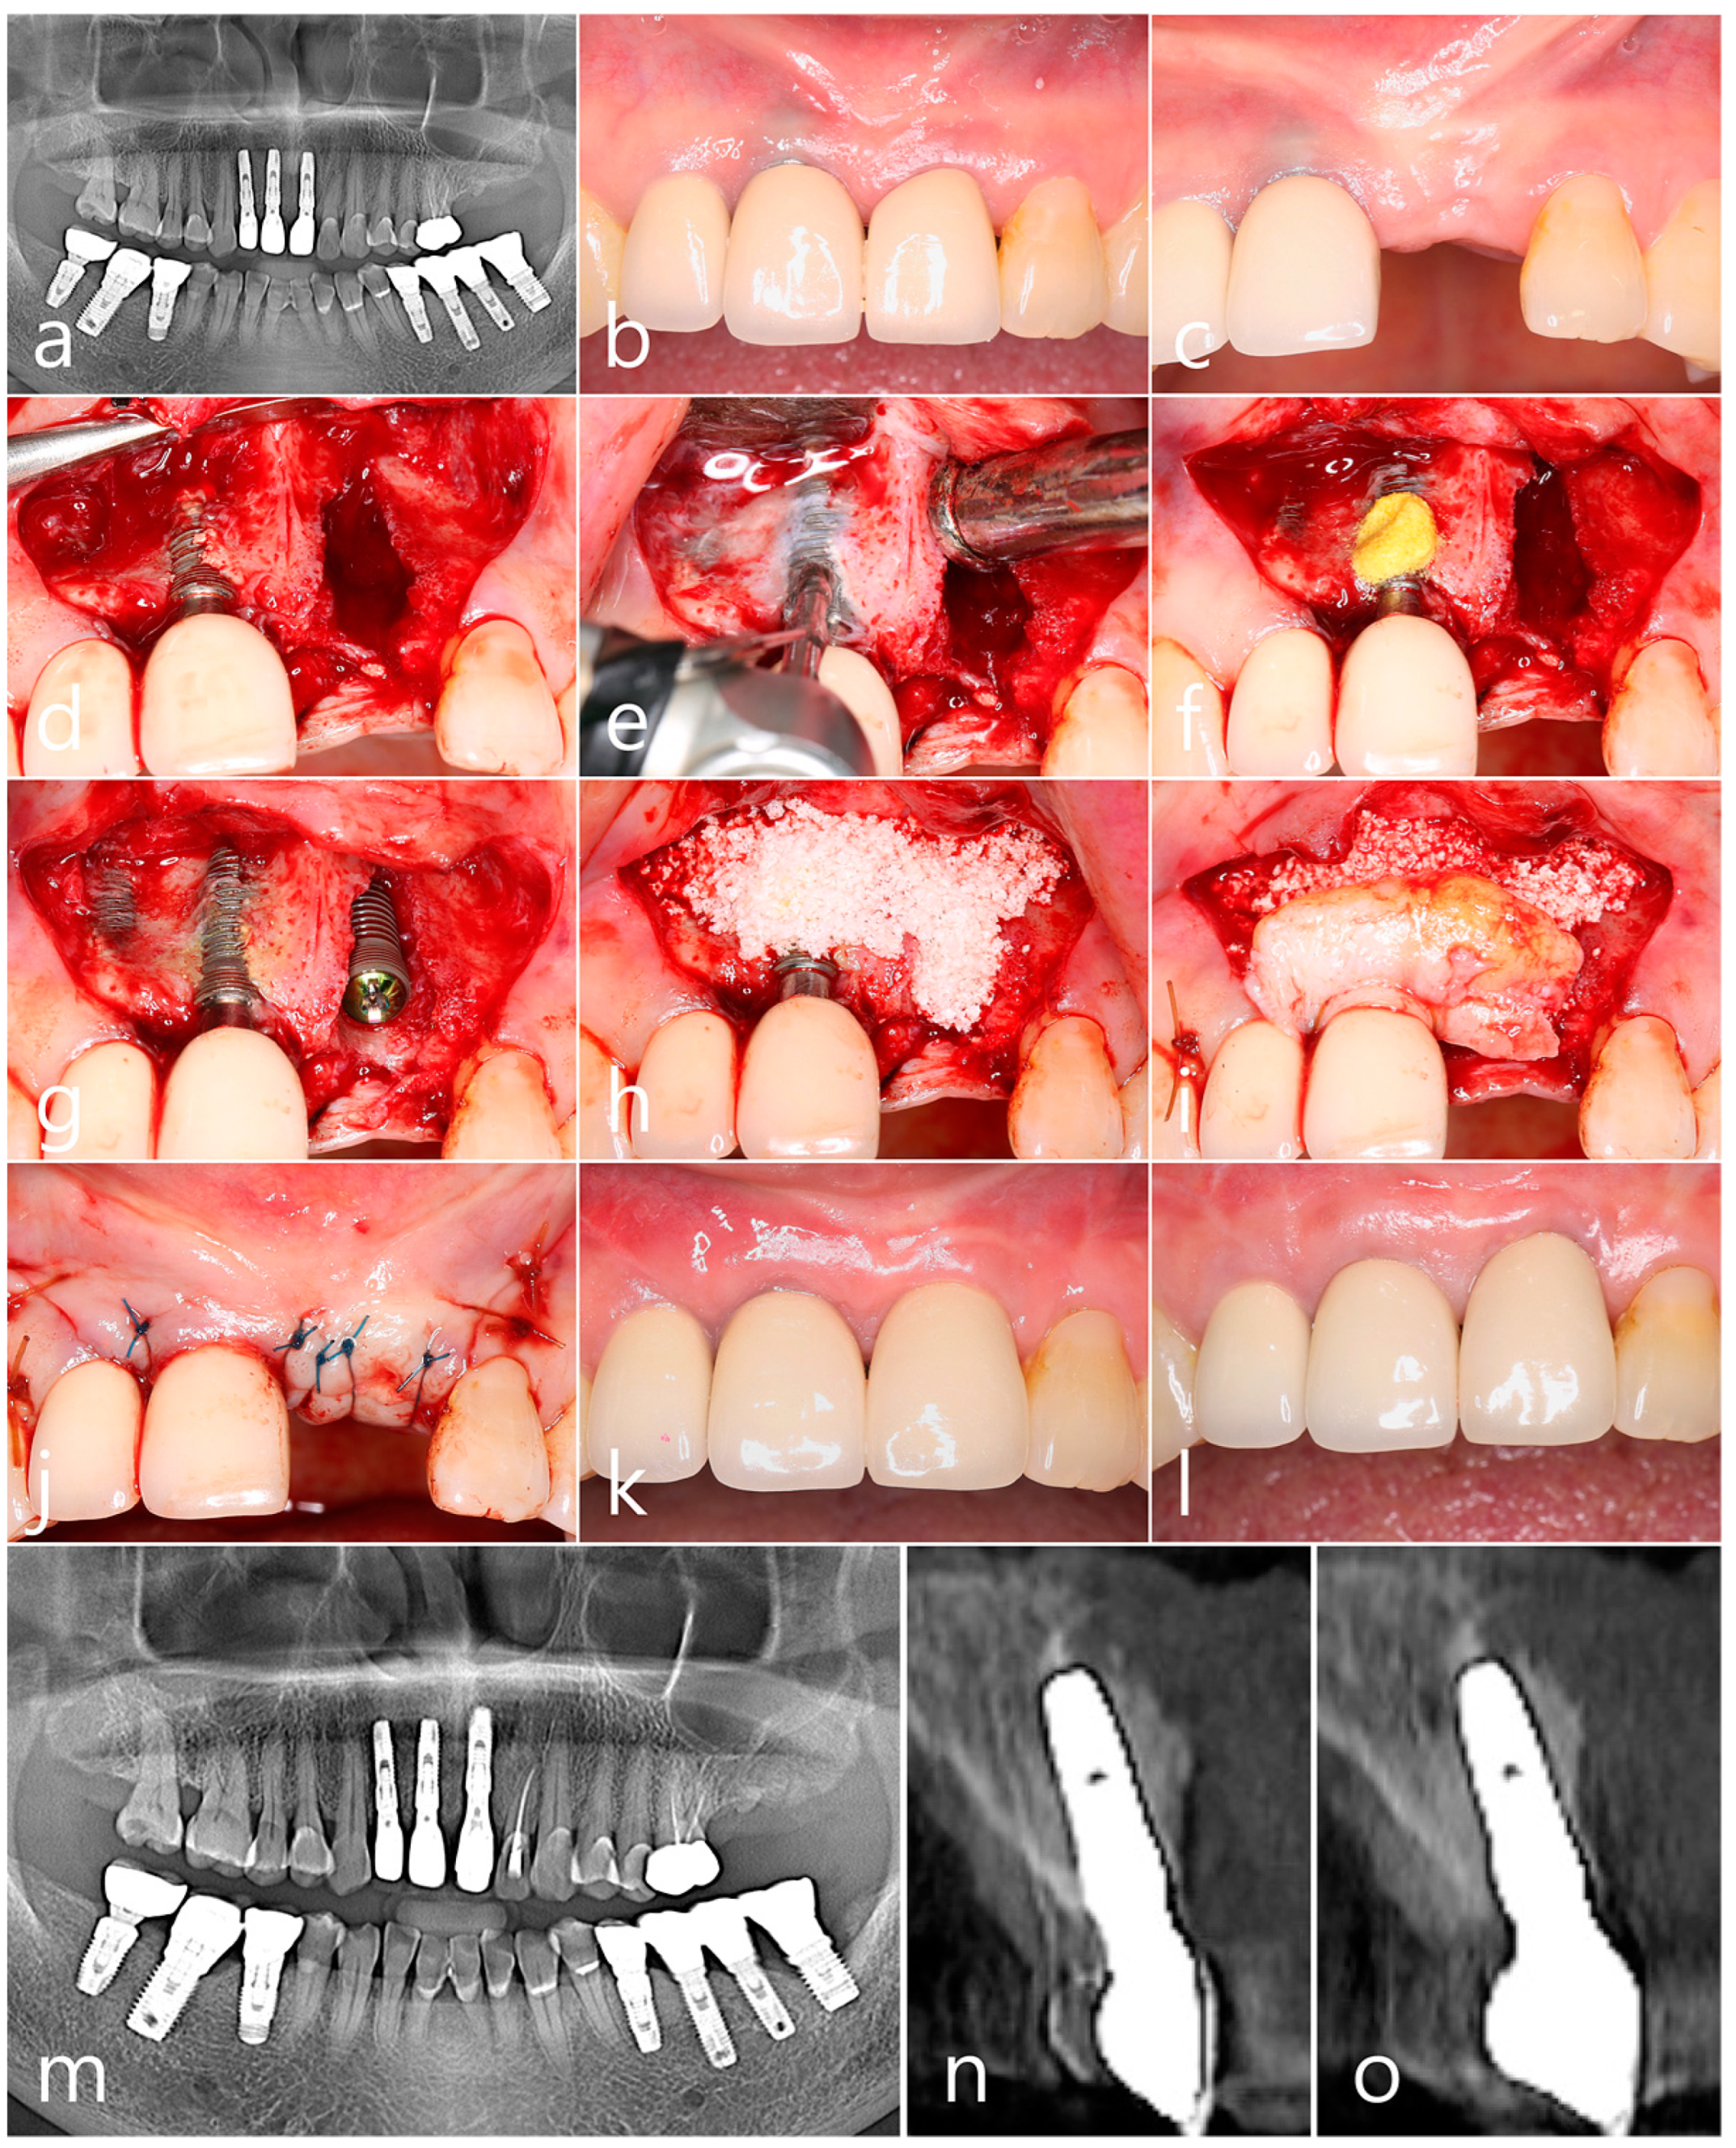

2.3. Case 3